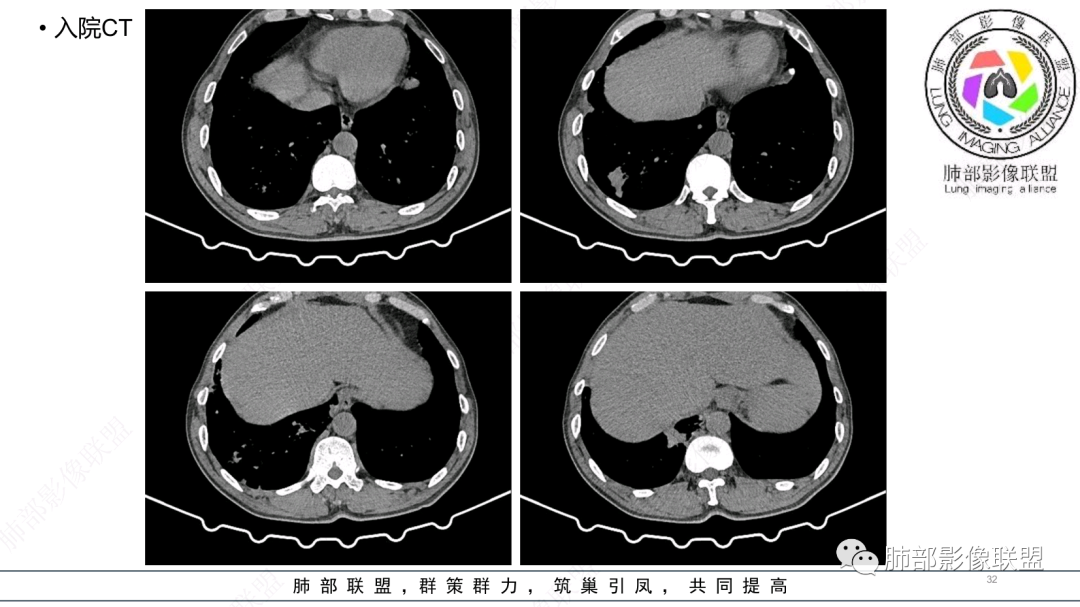

中老年男性,发病一周,发热,炎症指标明显增高,双肺支气管扩张基础,双肺可见多发结节、斑片状、团块状密度增高,边缘尚清。病灶分布与支气管关系密切,考虑支扩合并感染,铜绿,NTM、奴卡、曲霉等,环卫工人,可能接触腐败物较多,考虑曲霉可能大,鉴别奴卡。

中老年男性,发病一周,发热,炎性指标高,职业环卫工人,两肺弥漫分布肉芽肿结节病变,以胸膜下及支气管血管束分布为主,两肺多发支气管扩张,奴卡,结核,曲霉。

男性,56岁,清洁工,临床表现咳嗽咳痰发热。胸部影像:两肺散在斑片、结节及实变影,大部分沿气道分布,以下肺为著并伴发多发支气管扩张及囊腔影,实验室检查白细胞增高,考虑感染性病变,曲霉、铜绿及NTM。

56岁,工作性质:环卫工人。主诉:咳、痰、喘、发病一周。急性起病(或者慢病+AE),呼吸道感染症状。化验指标白细胞、中性、CRP明显升高。影像学显示多灶性,有柱状支扩,囊状支扩等结构肺病,责任细菌主要考虑铜绿假单胞菌,不排除合并其他细菌以阴杆为主;存在树芽影,发热,炎症沿支气管束分布,是否合并TB?真菌?;树芽伴发热支原体感染也要需要考虑进去;全肺多灶性炎症,部分病灶周围有晕,右上叶疑似反晕,内部疑似有丝,右下肺考虑存在粘液栓,加之环卫工工作性质,考虑霉菌,主要考虑曲霉。

两肺支扩,两肺沿支气管分布多发结节、树芽及团块,边缘模糊,部分支气管管壁增厚,考虑气道侵袭性曲霉菌,鉴别铜绿、奴卡、结核。

CT:双肺延支气管血管束分布斑片状、团块状、树芽状密度增高影,部分边界模糊,支气管扩张、部分管壁增厚。考虑气道吸入细菌性感染,铜绿假单孢?